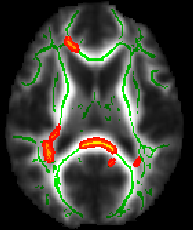

一、VBM 脑灰质密度分析

包括预处理、指标提取、统计分析、结果汇报与呈现

Figure 1. 大脑灰质密度差异示意图